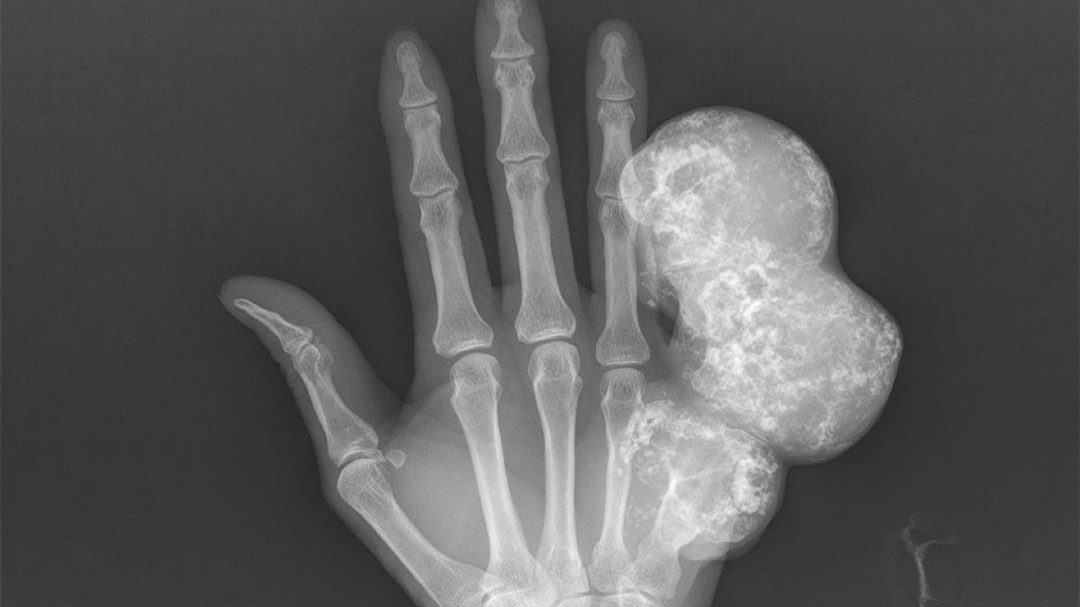

骨腫瘤有什么癥狀有哪些 骨腫瘤的早期癥狀圖片最新

骨腫瘤有什么癥狀有哪些?今日。程序員手疼7年查出骨腫瘤這一話題引發(fā)大家關(guān)注,骨腫瘤是怎么引起的?有什么影響?不少小伙伴對(duì)此很是好奇。下文小編整理了相關(guān)資訊,歡迎大家查閱。